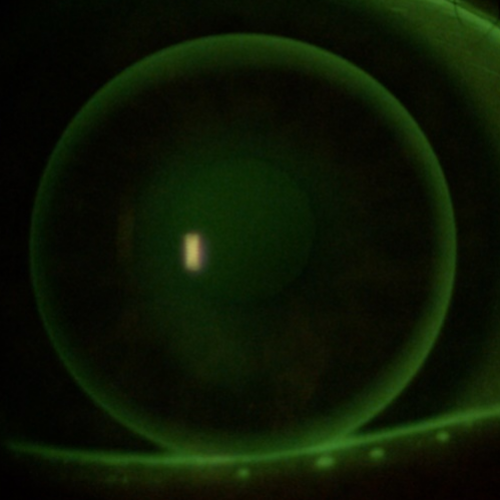

Contattologia

La Contattologia è l’insieme delle tecniche di studio volte all’applicazione di lenti a contatto attraverso l’uso di una strumentazione altamente professionale e all’avanguardia tali da permettere, a coloro che ne utilizzano, maggior sicurezza e personalizzazione.